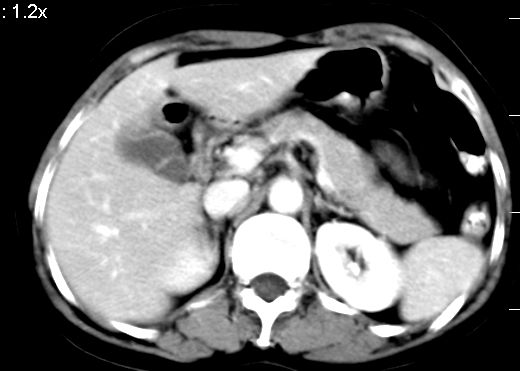

双肾灌注良好,代谢增快,动脉期肾盂见造影剂,左肾下极背侧见一略低密度病灶,延迟期见似不强化囊肿,双侧肾上腺未见异常。

1、胆囊炎(轻度)。

2、肝s8段结节,考虑小血管瘤。

3、左肾下极低密度灶,考虑囊肿可能性大,建议随访,除外小肾癌(无强化可以基本除外)。

4、目前ct表现尚不能解释患者上腹部疼痛,建议上消造影检查,除外胃炎等疾患。